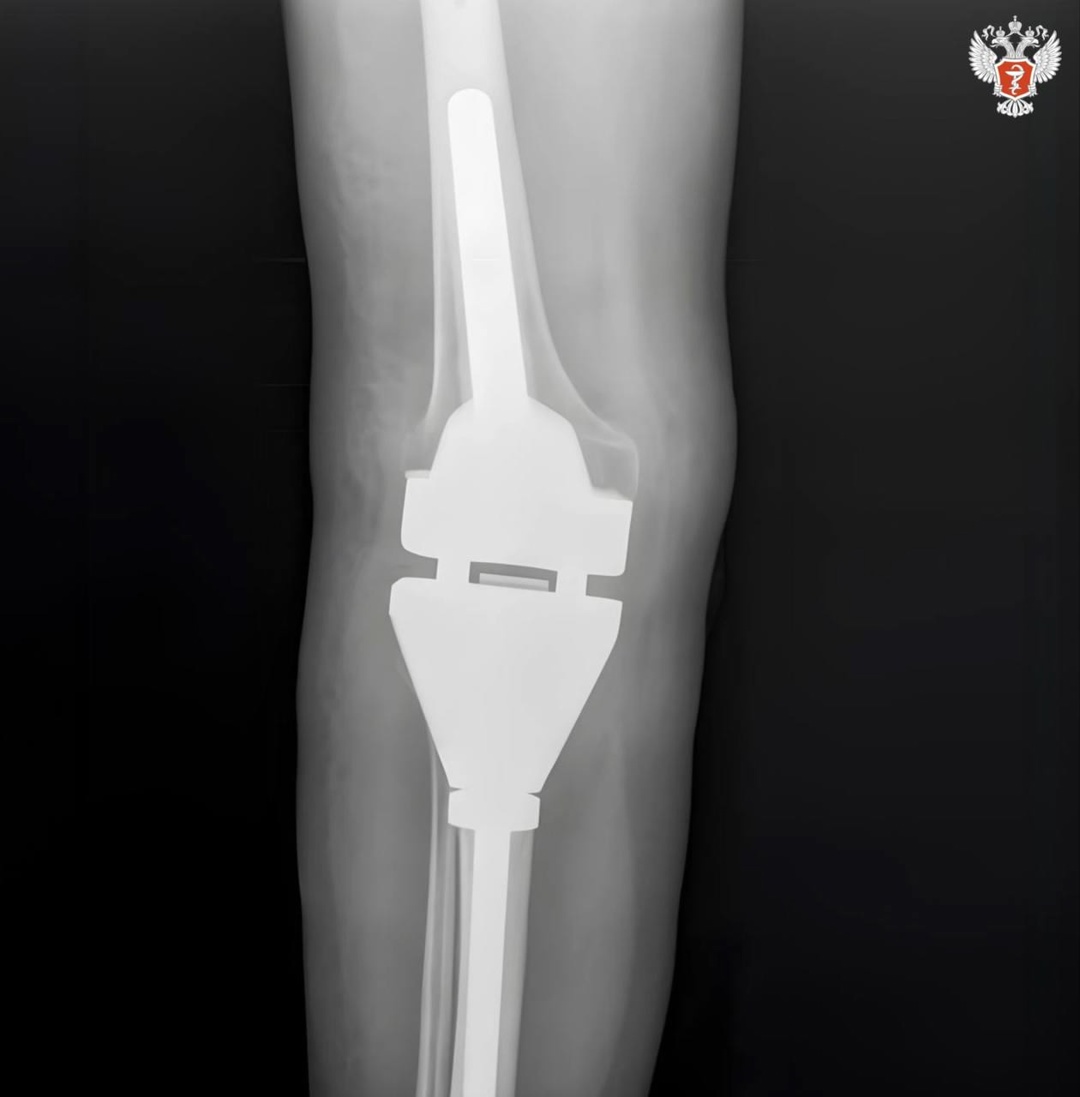

У 56-летней пациентки Самарского областного клинического онкологического диспансера диагностировали гигантоклеточную опухоль верхней трети правой большеберцовой кости.

После специалисты установили эндопротез, произведенный полностью из российских материалов в НИИ бионики и персонифицированной медицины СамГМУ Минздрава России.

🔵 Особенность онкологического эндопротезирования — после удаления опухоли эндопротезом необходимо заместить обширный участок.